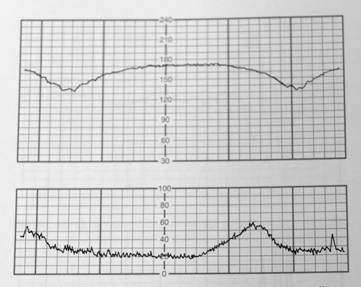

詳解

破題關鍵

這張圖的解題核心在於判斷胎兒心跳減速(deceleration)與子宮收縮(contraction)之間的「時間關係」。仔細觀察胎兒心跳下降的最低點(nadir)是否發生在子宮收縮高峰之後,這是判斷晚期減速的關鍵視覺線索。

選項拆解

【107-1 醫學(六) 第52題】承上題,下列四者中最可能的臨床意義為何?

晚期減速是胎兒缺氧的警訊,通常與胎盤功能不佳有關。